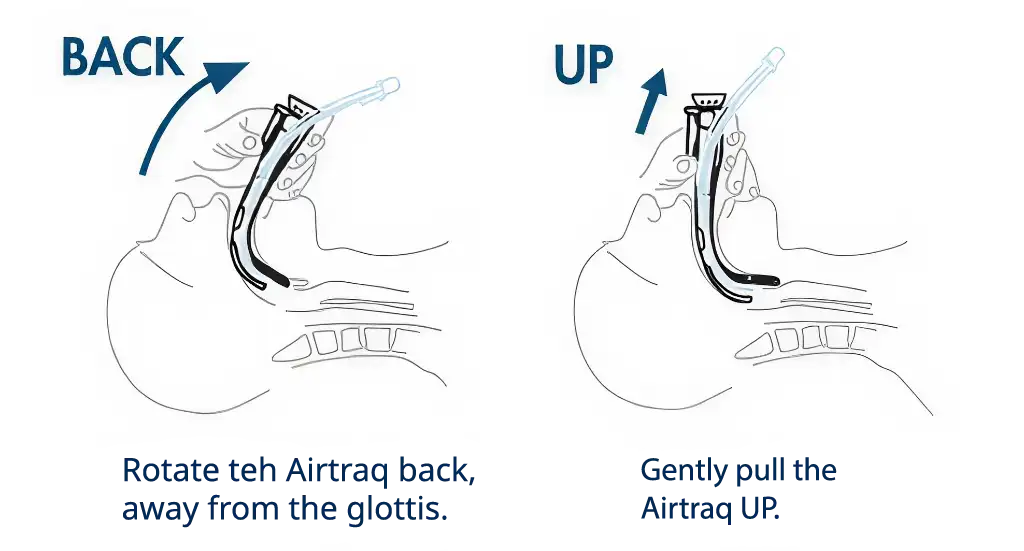

Location of glottic structures

If vocal cords are not seen it is very likely that Airtraq has been inserted TOO DEEP, if so perform the following maneuver:

A gent lift of the Airtraq causes the glottis to open and drops the interarytenoid notch below the middle of the image (optimal position for successful ETT insertion)

Airtraq inserted Too Deep

Airtraq inserted too close to the glottis or too posterior in front of the oesophagus